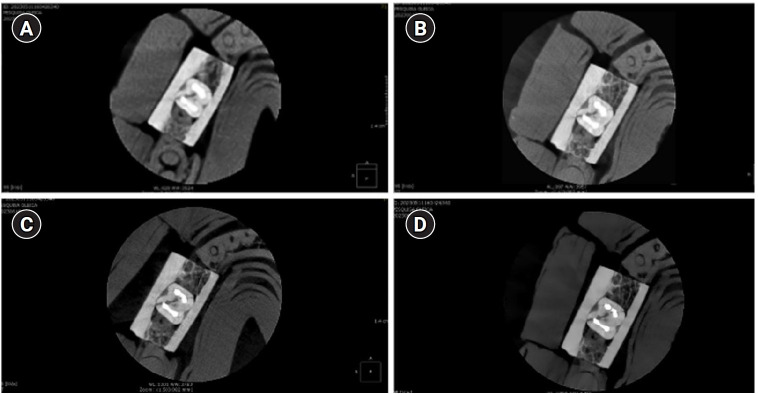

Methods: Twenty human molar teeth filled with gutta-percha were placed into artificial alveoli created in bovine ribs. The sample was divided into two groups based on the presence or absence of intraradicular posts in the distal roots. CBCT scans were obtained using four acquisition protocols with varying voxel sizes (0.28, 0.2, 0.125, and 0.80 mm). Following the creation of controlled fractures using a chisel and hammer, CBCT imaging was repeated, resulting in 160 images. Five examiners assessed the images using OnDemand software (KaVo Dental GmbH). Sensitivity, specificity, and accuracy were calculated for each examiner, CBCT protocol, and post-condition. Statistical comparisons were performed using Cochran's Q test and McNemar test, and a significance level of 5%.